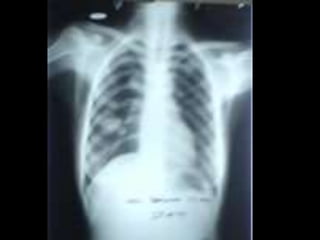

• C’est un téléthorax de face objectivant de

multiples opacités de tonalité hydrique, de taille

miliaire et micronodulaire diffuse, intéressant les 2

champs pulmonaires.

• L’index cardio-thoracique est normal, les culs de

sacs pleuraux sont libres et on note l’absence de

lésions osseuses visibles .Conclusion : syndrome

interstitiel diffus bilatéral évoquant une miliaire

tuberculeuse en 1er lieu. Diagnostic différentiel :

miliaire carcinomateuse, pneumoconiose (maladie

professionnelle)

• CAT : Echographie abdomino- pelvienne (car il

existe des miliaires spléniques, hépatiques ou

rénales. TDM thoracique, scintigraphie osseuse°